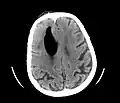

Large pneumocephaly secondary to surgical wound

Pneumocephaly